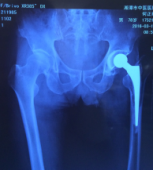

病例3 患者何某,男性,78歲,左髖關(guān)節(jié)置換術(shù)后6年,出現(xiàn)疼痛、活動(dòng)困難1年,診斷為“左髖關(guān)節(jié)置換術(shù)后假體松動(dòng)”,患者身體瘦弱,既往有高血壓病、冠心病、心肌梗死等病史,進(jìn)行髖關(guān)節(jié)翻修手術(shù),存在一定的風(fēng)險(xiǎn),必須較好的控制手術(shù)節(jié)奏,同時(shí)確保手術(shù)順利和病人生命安全,專家團(tuán)隊(duì)匯集麻醉科、內(nèi)科、ICU團(tuán)隊(duì),進(jìn)行了詳盡的手術(shù)中、手術(shù)后的計(jì)劃和預(yù)案,手術(shù)得以順利實(shí)施,術(shù)后經(jīng)過骨科、內(nèi)科、ICU團(tuán)隊(duì)的配合,患者得到良好的恢復(fù)。

術(shù)前X線片

術(shù)后X線片